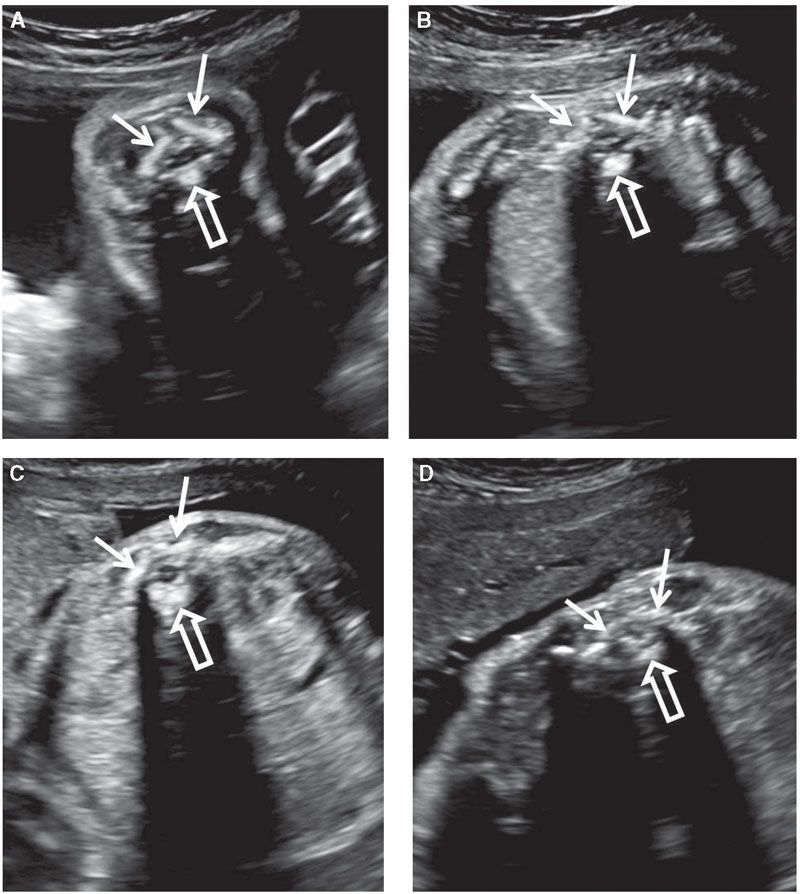

Baby spine Sonography, Ultrasound, Pediatrics